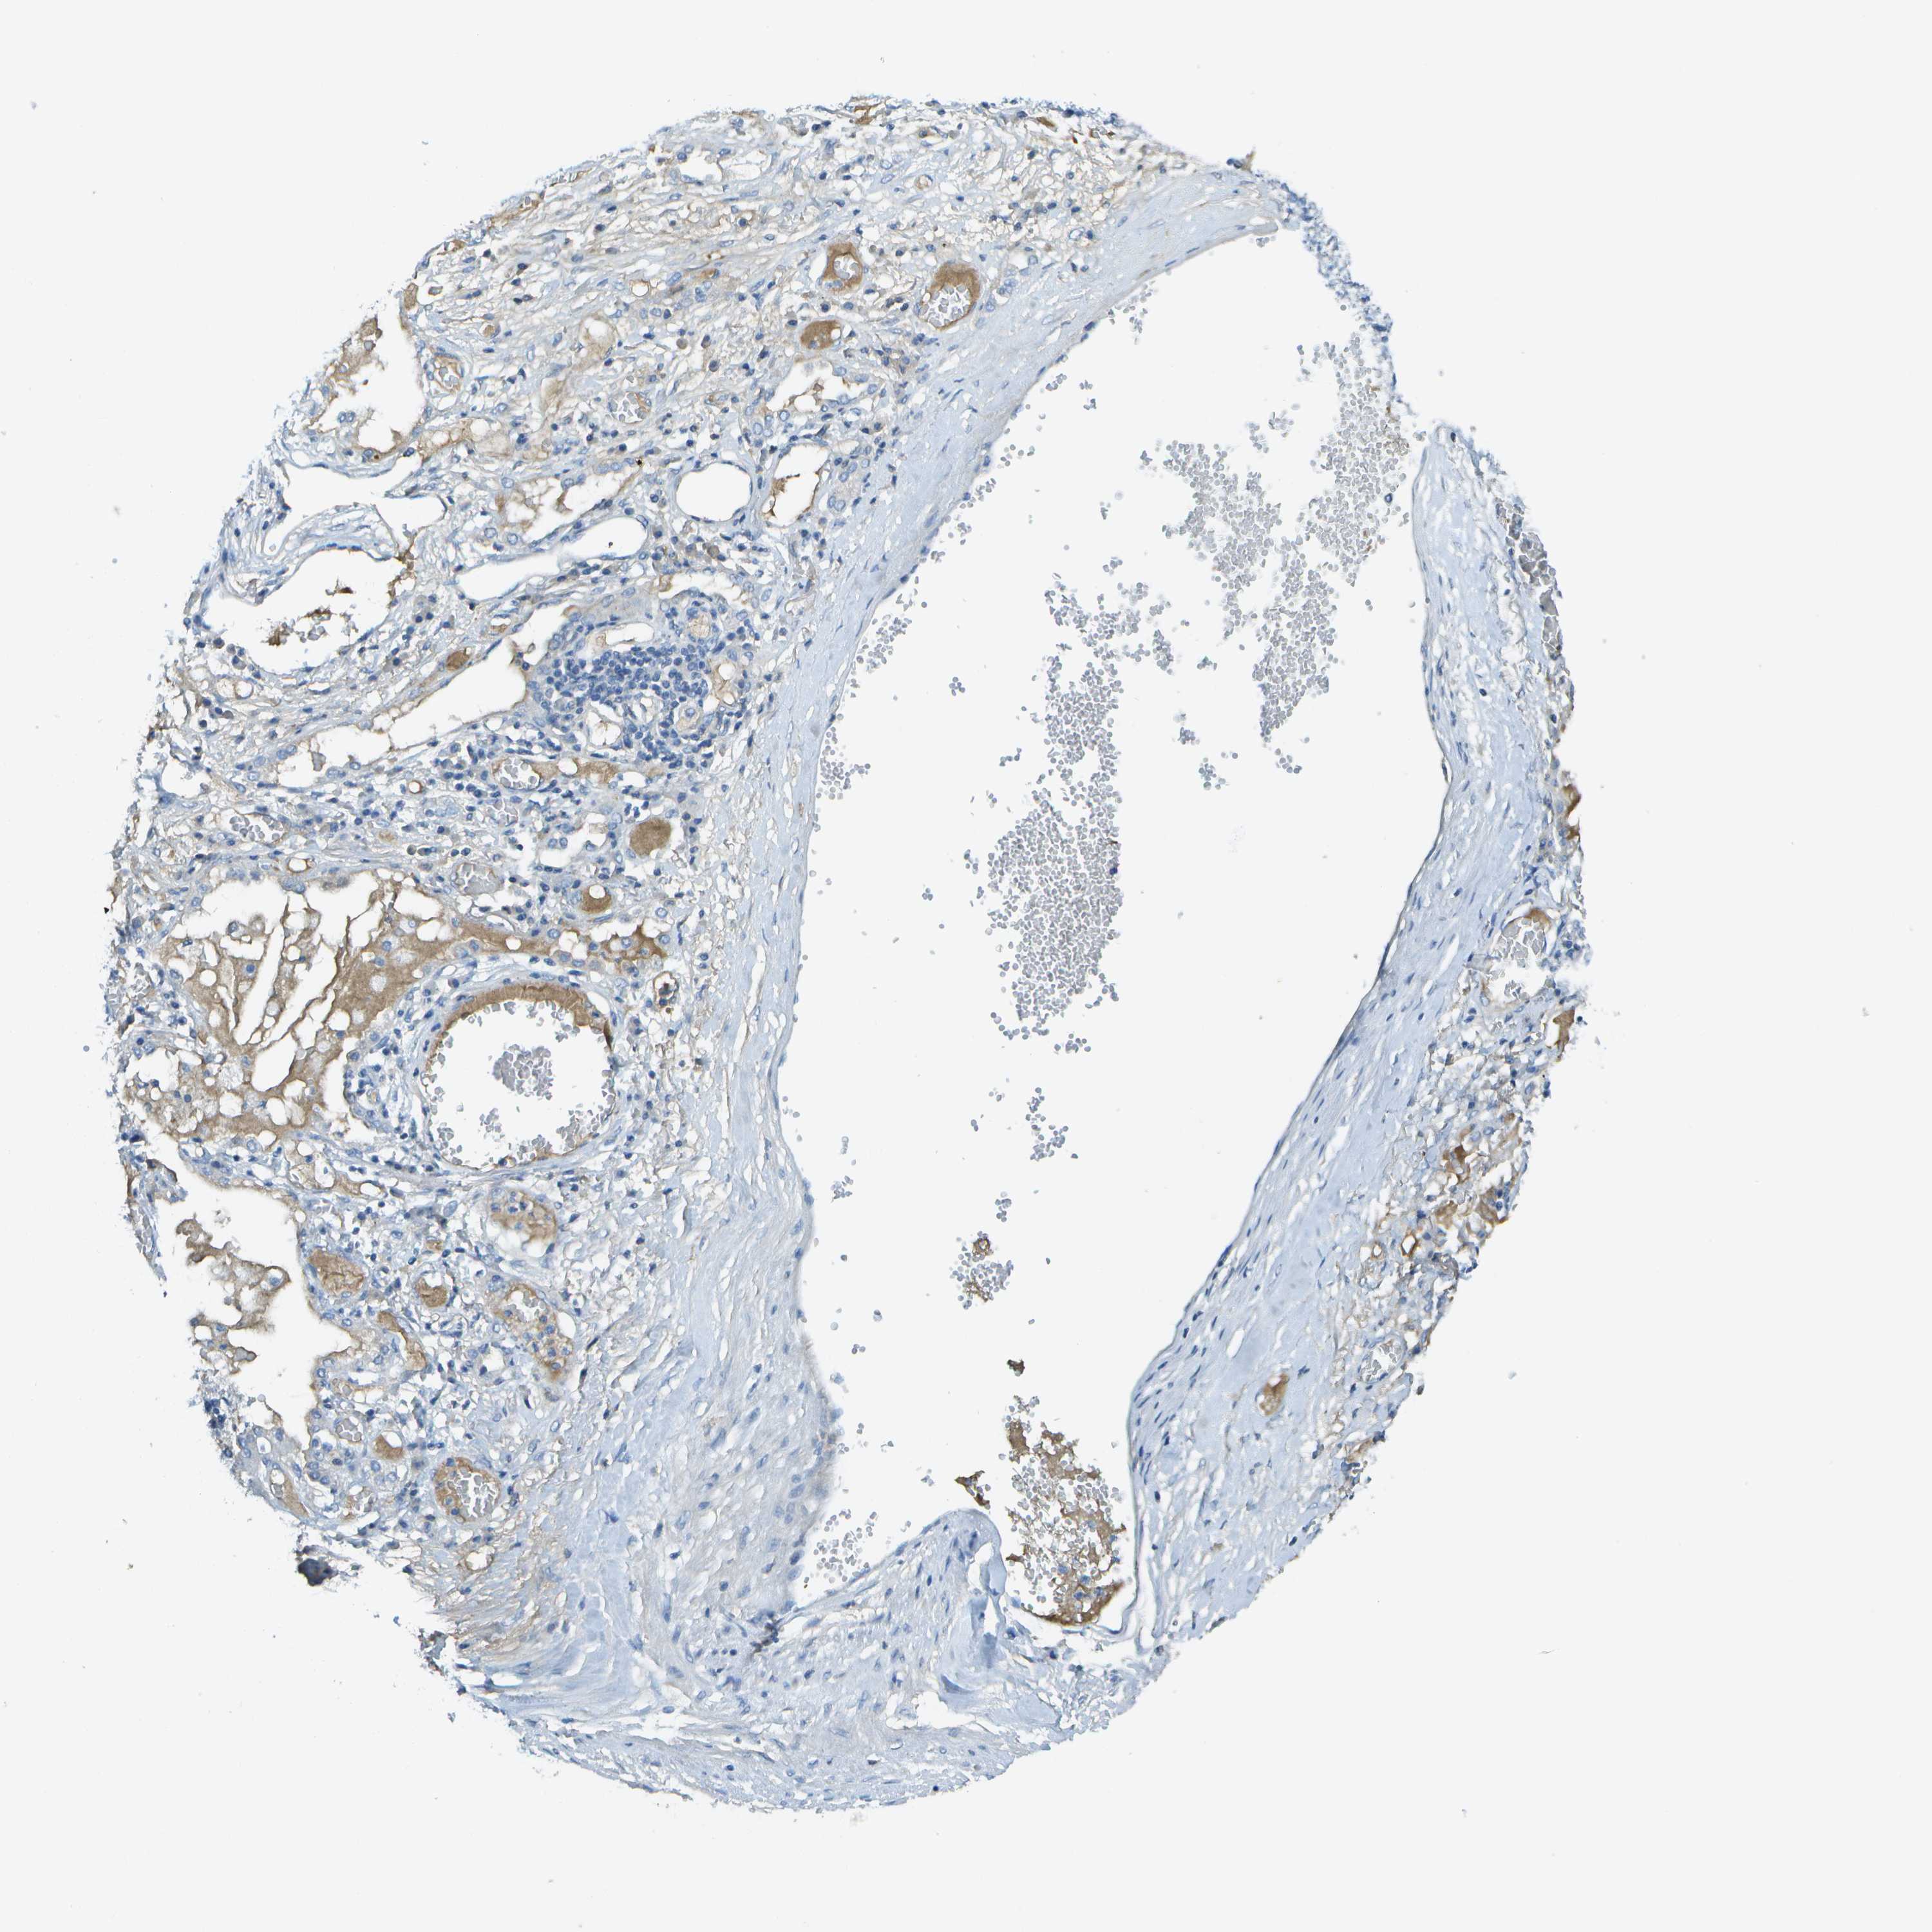

LUNG SQUAMOUS CELL CARCINOMA (TCGA) - Interactive survival scatter ploti

The Survival Scatter plot shows the clinical status (i.e. dead or alive) for all individuals in the patient cohort, based on the same data that underlies the corresponding Kaplan-Meier plots. Patients that are alive at last time for follow-up are shown in blue and patients who have died during the study are shown in red.

The x-axis shows the expression levels (FPKM) of the investigated gene in the tumor tissue at the time of diagnosis. The y-axis shows the follow-up time after diagnosis (years). Both axes are complimented with kernel density curves demonstrating the data density over the axes. The top density plot shows the expression levels (FPKM) distribution among dead (red) and alive patients (blue). The right density plot shows the data density of the survived years of dead patients with high and low expression levels respectively, stratified using the cutoff indicated by the vertical dashed line through the Survival Scatter plot. This cutoff is automatically defined based on the FPKM cutoff that minimizes the p-score. The cutoff can be changed by dragging the vertical line or by entering a cutoff value in the square labeled "Current cut-off".

Under the Survival Scatter plot the p-score landscape (black curve; left axis) is shown together with dead median separation (red curve; right axis). Dead median separation is the difference in median mRNA expression between patients who have died with high and low expression, respectively. It is calculated as follows: median FPKM expression of dead patients with high expression - median FPKM expression of dead patients with low expression. This is intended to aid the user in visually exploring custom cutoffs and the associated p-scores and dead median separation.

Individual patient data is displayed and can be filtered by clicking on one or more of the category buttons on the top of the page. Categories describing expression level and patient information include: high, low, alive, dead, female, male and tumor stages. The scale of the x-axis can be toggled between linear and log-scale by clicking on the "x log" button. Mouse-over function shows TCGA ID, patient information and mRNA expression (FPKM) for each patient.

& Survival analysisi

Kaplan-Meier plots summarize results from analysis of correlation between mRNA expression level and patient survival. Patients were divided based on level of expression into one of the two groups "low" (under cut off) or "high" (over cut off). X-axis shows time for survival (years) and y-axis shows the probability of survival, where 1.0 corresponds to 100 percent.

C1S is not prognostic in Lung Squamous Cell Carcinoma (TCGA)

Best expression cut offi

Based on the FPKM value of each gene, patients were classified into two groups and association between prognosis (survival) and gene expression (FPKM) was examined. The best expression cut-off refers the FPKM value that yields maximal difference with regard to survival between the two groups at the lowest log-rank P-value. Best expression cut-off was selected based on survival analysis .

When clicking on this number, the vertical dashed line indicating cut-off, the interactive survival plot, and the Kaplan-Meier curve will be adjusted to show results based on the best expression cut-off.

: 128.02

P scorei

Log-rank P value for Kaplan-Meier plot showing results from analysis of correlation between mRNA expression level and patient survival.

N/A

TCGA RNA samplesi

RNA-seq data is reported as average FPKM (number Fragments Per Kilobase of exon per Million reads), generated by the The Cancer Genome Atlas (TCGA) .

Normal distribution across the dataset is visualized with box plots, shown as median and 25th and 75th percentiles. Points are displayed as outliers if they are above or below 1.5 times the interquartile range. FPKM values of the individual samples are presented next to the box plot.

Average pTPM 218.7

Number of samples 489